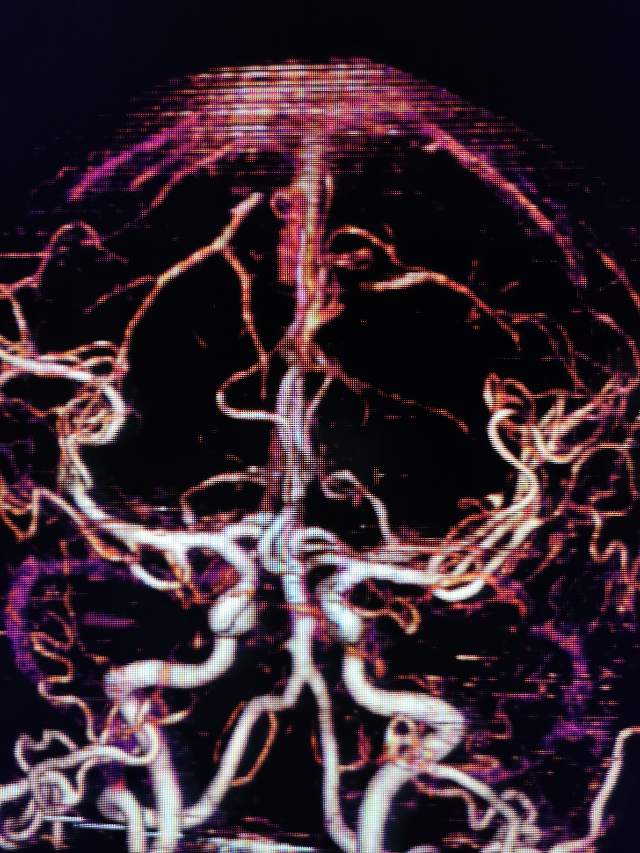

进一步行DSA检查后发现:左侧颈内动脉起始部有一个颈动脉蹼。这个血管内的“蹼”,是一个薄片状的结构,类似掌部的“蹼”,它会在颈内动脉起始部产生“扰流效应”,瘀滞的血流存在栓子形成和脱落的风险………,冲散的栓子可以“天女散花”,也可以“天上掉下石头”,这不,这位兄弟就被掉下的石头砸到颅内的功能区了,手脚语言都砸坏了。

向家属讲明来龙去脉之后,家属和患者本人积极寻求进一步的治疗。于是限期给予病变简单外科干预,消除了潜在的风险,远端的有效血流也相对增加了(有利于功能恢复),再也不用担心“天上”掉石头下来砸着“脑袋”了。